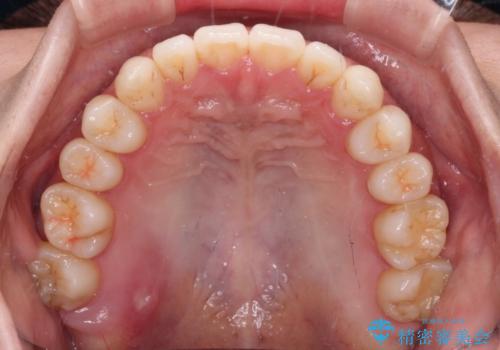

インビザラインで口を閉じやすく

- 下唇に上の前歯が当たることを気にして来院された患者様です。

上顎の親知らずを抜去し、歯列全体を後方に移動させるとともに、IPR(歯と歯の間を削る)を行うことで口元の閉じにくさを改善していくこととしました。

咬合力が強く、マウスピースを介した咬み込みが顕著であったため、奥歯の咬みにくさやIPRのスペースが改善しにくく、治療期間が思った以上にかかってしまいました。